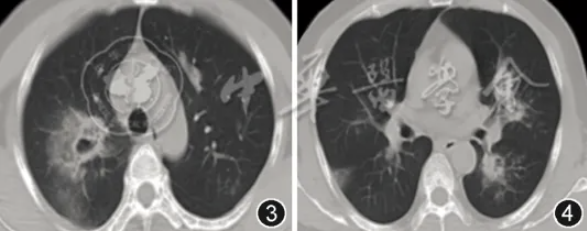

镜下局部灌注AmBD治疗需签署知情同意书并向医务处备案。首次灌注术前1~3 d要雾化吸入AmBD进行诱导治疗以避免灌注中发生不良反应。文献[10, 11, 12]建议灌注浓度为0.025%~0.125%,并确保每处靶点分配至少2.5 mg,重要靶点可以超过5 mg。本例双肺广泛受累,常规容量难以覆盖全部病灶。初期采用10~20 mg AmBD溶于20~30 ml注射用水进行分段灌注,但影像仍显示部分区域进展,考虑与病灶分布广泛、药液总量不足以及菌栓无法短期内清除有关。后续调整方案为:AmBD 20~30 mg以注射用水溶解后加入生理盐水至120~200 ml,按胸部CT肺段受累的严重程度进行分段灌注,具体方法为:双肺每个肺段按胸CT显示受累程度分为0~4分,将AmBD灌注溶液按分值占比分配至需要灌注的段支气管,每周2~3次。经积极清创与3次大容量灌注治疗后,患者所有菌栓完全清除,影像学表现明显改善(图13,14)。整个治疗过程中未出现呼吸困难、咯血、胸痛、心律失常、心力衰竭、肾功能不全等并发症,耐受良好。

图13,14 2025年4月2日胸部CT示右上叶空洞基本闭合,双肺实变影较前吸收